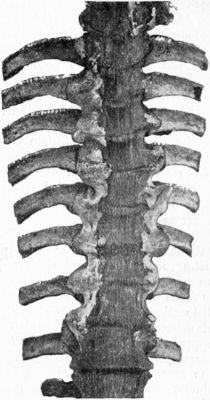

210.Tuberculous Osteomyelitis affecting several Vertebræ at Thoracico-Lumbar Junction432

211.Osseous Ankylosis of Bodies (a) of Dorsal Vertebræ, (b) of Lumbar Vertebræ following Pott's Disease434

212.Radiogram of Museum Specimen of Pott's Disease in a Child435